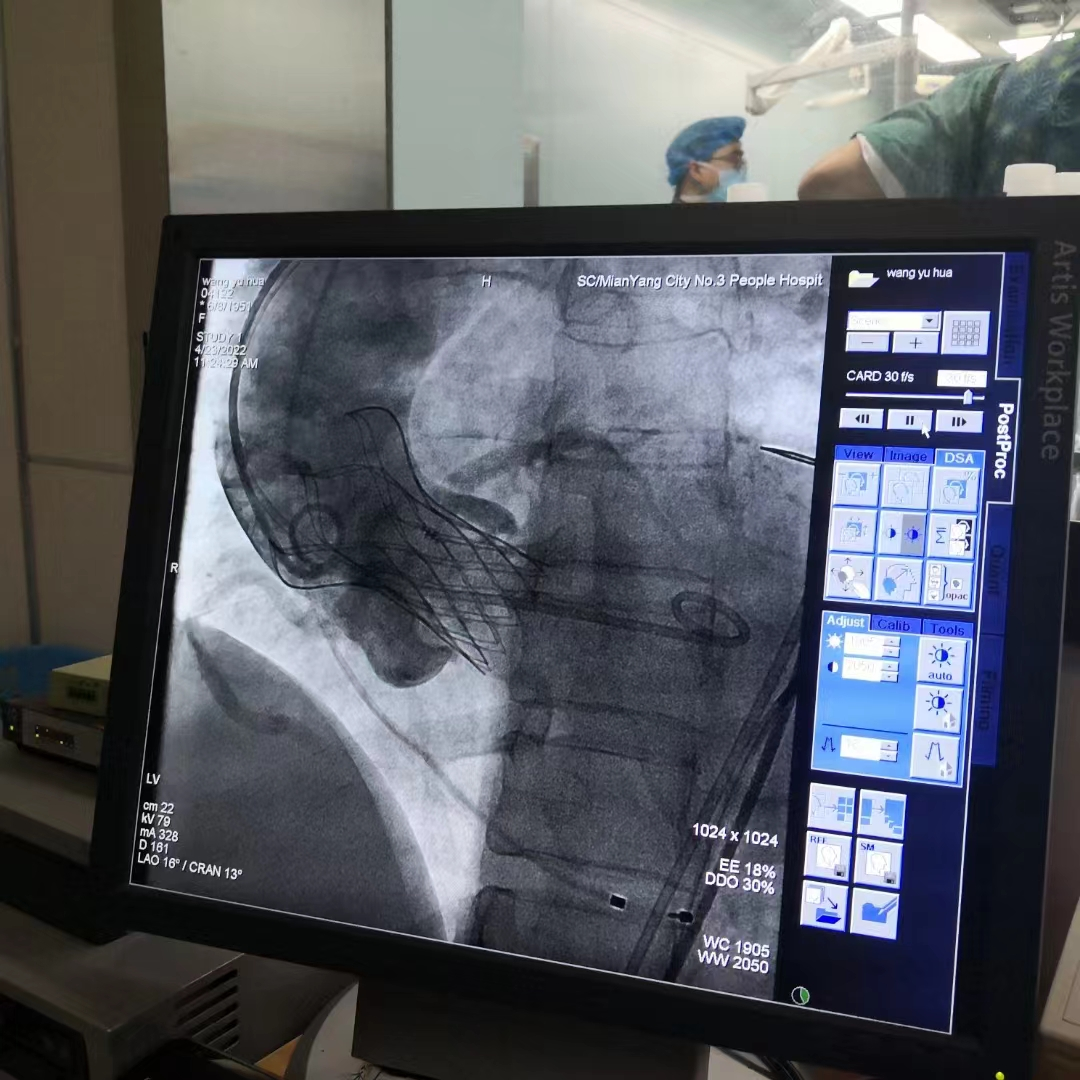

主动脉瓣狭窄(AS)是一种常见的心脏瓣膜病,随着年龄的增长,患者数量显著增加。活动后胸闷气促是该病最常见的症状,而严重AS患者可能发生猝死。药物治疗对AS的治疗效果非常有限,因此手术是唯一有效的治疗方式。传统的心脏手术需要体外循环、心脏停跳,且需要开胸进行,创伤大、风险高、恢复慢。而经导管主动脉瓣置换术(TAVR)是一种微创的介入手术,术后24-48小时可以下床活动,伤口一般在5-6天内愈合。

TAVR手术使用微创方法,将新的人工瓣膜压缩到一根细的管子中,沿着血管输送到达心脏主动脉瓣处,然后将人工瓣膜推出或扩开固定在病变的主动脉瓣处,以完全替代病变瓣膜的功能。